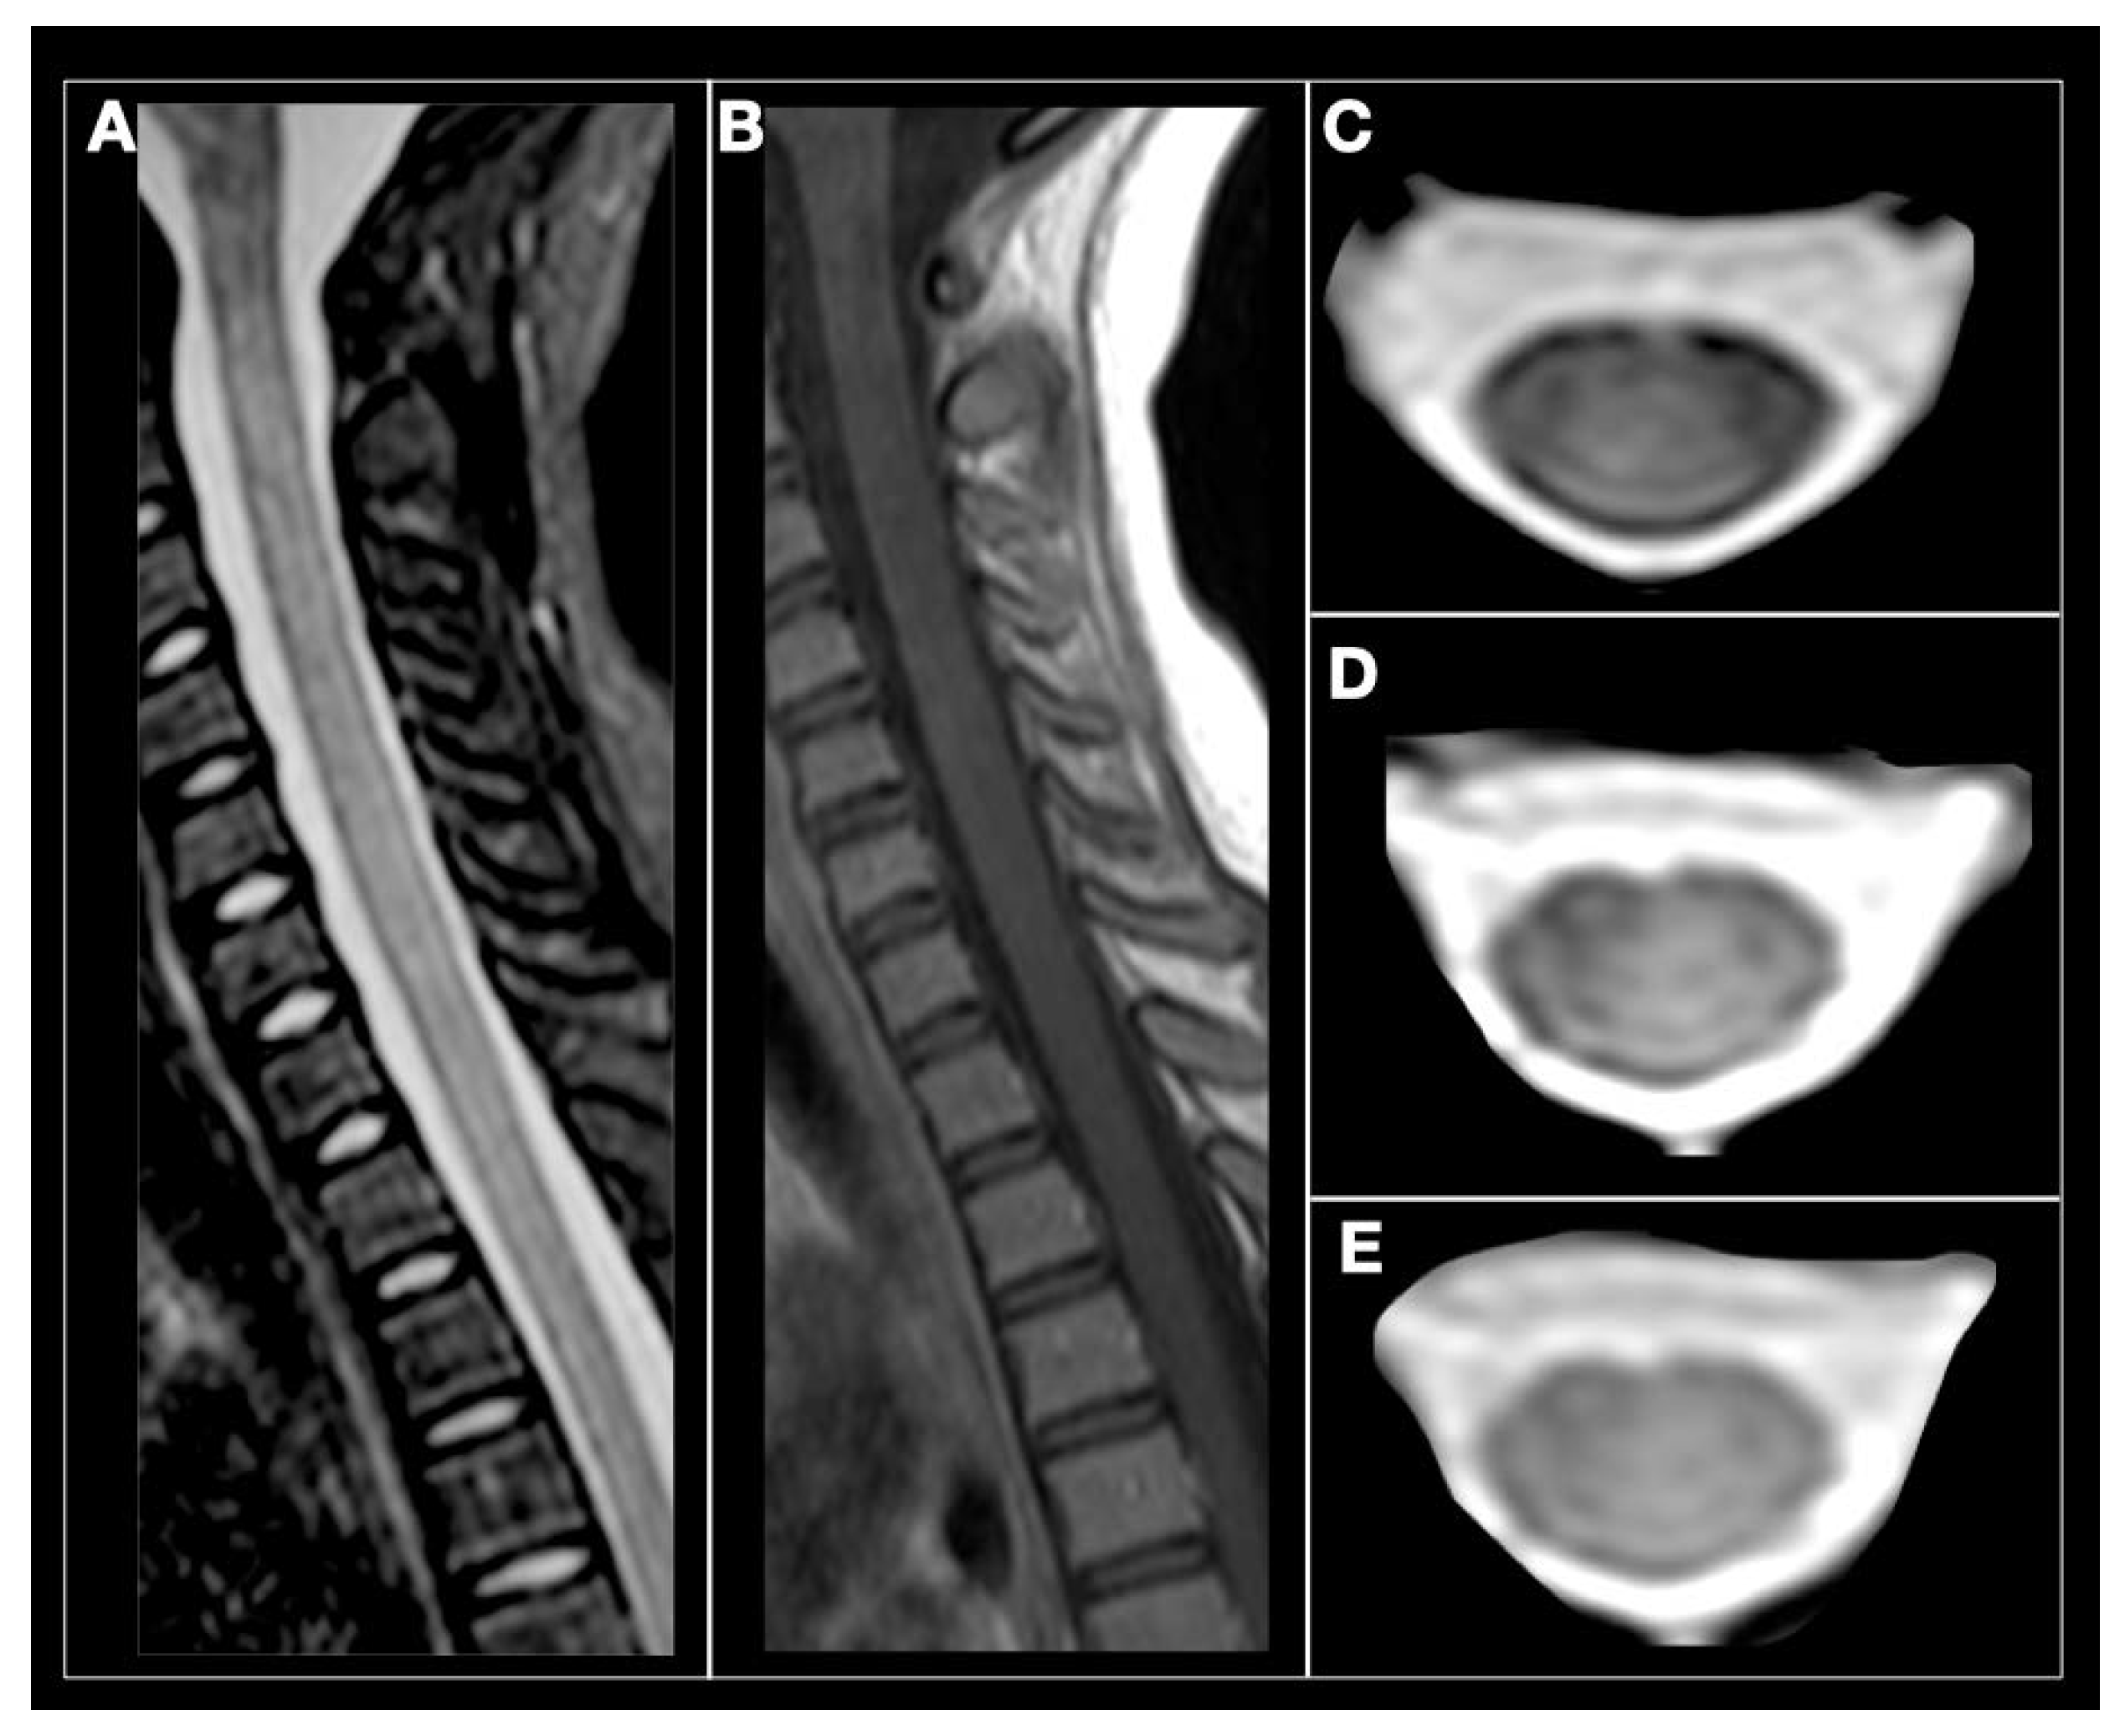

Figure 4.

Anti-MOG antibody myelitis. A 12-year-old girl with relapse in the cervical spine. (A) sagittal STIR, subtle and diffuse hyperintensity of the cervical spinal cord. (B) Sagittal T1-weighted, spinal cord is isointense without contrast enhancement. (C–E) axial T2-weighted images showing subtle and diffuse spinal cord hyperintensity (Courtesy Dr. Angeles Schteinschnaider).

Approximately half the patients with MOG ab-associated disease present episodes involving the spinal cord [177,178]. The most common symptoms include paraparesis, and sensory and sphincter dysfunction. On MRI, LETM is frequent and short myelitis less common. Any segment of the spinal cord can be affected, although lesions are more frequent in the thoracolumbar and/or conus medullaris regions, as opposed to the more common cervicothoracic involvement observed in AQP4 ab positive and MS myelitis cases [178,179]. Anti-MOG ab associated myelitis is hyperintense on T2-weighted and iso-hypointense on T1-weighted sequences, showing contrast enhancement during acute phases in up to 70% of cases [172]; Figure 3 and Figure 4. MOG ab-related disease does not commonly result in cord necrosis or cavitations as observed in AQP4-mediated cases [134,175,178]. Due to the predilection for conus localization, bladder, bowel, and erectile dysfunction is observed in approximately 70% of patients [167]. In comparison to AQP4-IgG+ NMOSD, MOG ab disease myelitis appears to more focal and with better clinical outcome, although poor outcome with permanent disability has been described for both conditions [156]. Notably, anti-MOG ab serum titers follow disease activity levels, with significantly higher concentration during acute attacks than remission, further supporting the concept of their pathogenic role [172].